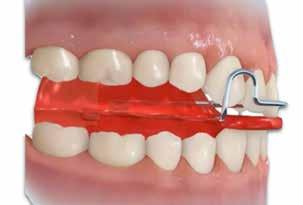

Fig. 118 > Apparecchio elastodontico all’interno del cavo orale: è possibile

apprezzare il grande lavoro che lo stesso svolge sulle strutture scheletriche, sui muscoli delle labbra e della lingua; di qui l’effetto tridimensionale della terapia elastodontica.